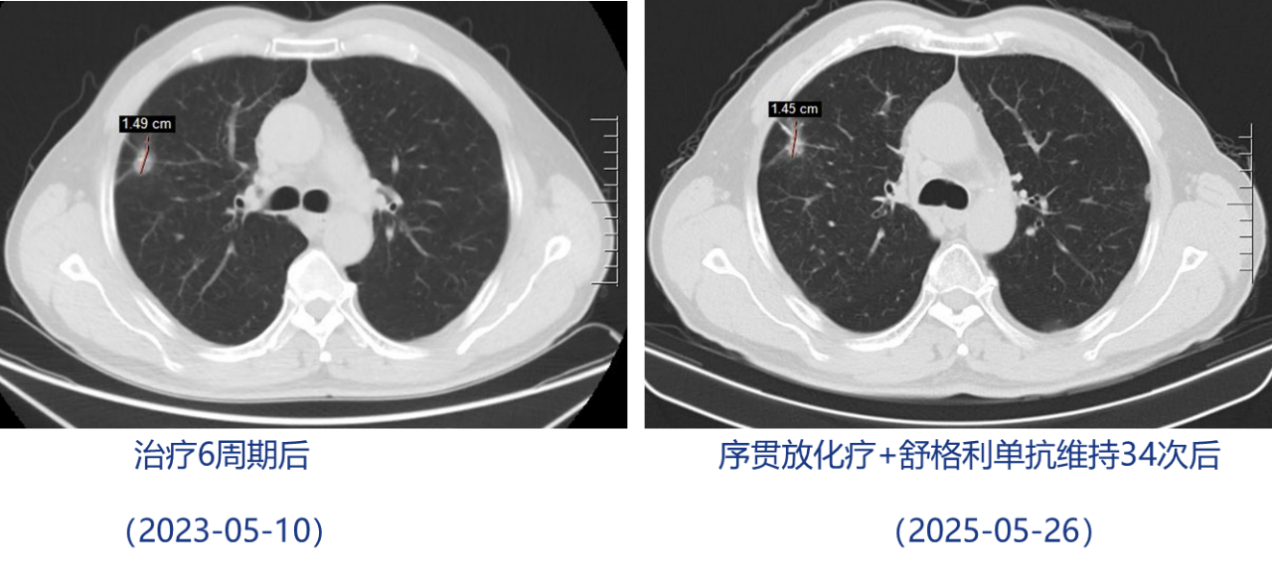

治疗6周期后复查,疗效评价为病情稳定(SD)。

免疫维持治疗:2023-05-19至2025-08-26,予舒格利单抗维持治疗,共36次。治疗过程中,患者出现甲状腺功能减退,给予优甲乐治疗后好转。至今,患者病情保持稳定。

治疗期间影像学结果(胸部CT):

本病例为一名74岁男性,诊断为ⅢB期KRAS G12C突变右肺腺癌,伴同侧肺门、纵隔及锁骨上淋巴结转移。患者一线化疗联合抗血管生成治疗2周期后达到PR,肺部肿瘤最大直径由2.2cm缩小至1.56cm;随后适时加予局部放疗,并配合免疫维持治疗延续疗效。至今,仍持续SD,无进展生存期(PFS)已逾3年,且生活质量良好。该案例充分彰显“免疫+”模式协同增效及拖尾效应,为局晚期KRAS G12C突变NSCLC实现长生存提供了可行范式。